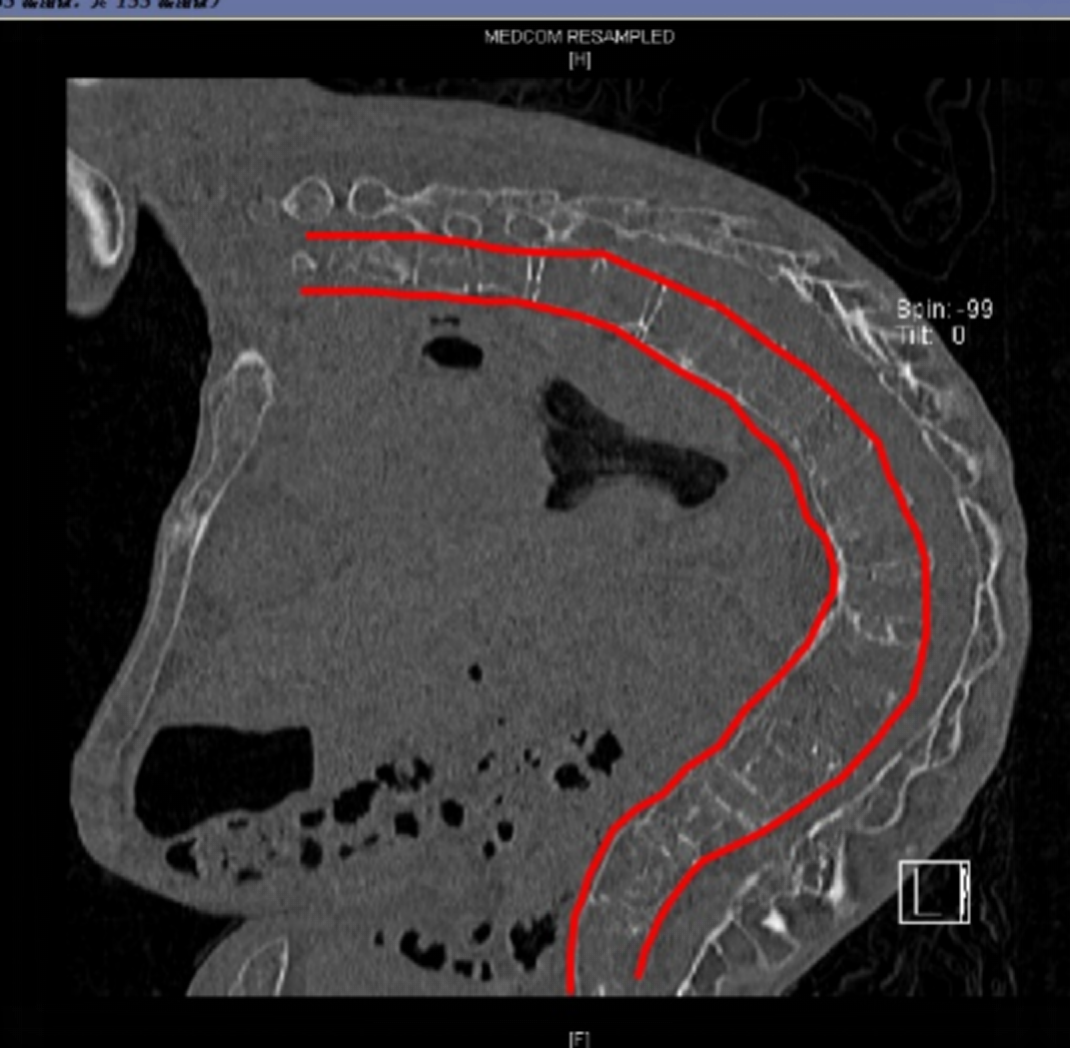

▲纤支镜引导下成功为苏先生实施经鼻腔气管导管置入

麻醉一科许文言副主任医师,评估气道情况时发现,情况比预想的更严重。患者脊柱严重弯曲,呈僵硬的C形,无法进行常规气管插管。

许文言、郭艳华副主任医师在充分评估、完备预案后,决定为苏先生实施纤支镜引导下的清醒状态经鼻腔气管插管术。